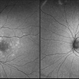

- Cloquet Canal, punctum caecum, stilling's canal, hyaloid membrane

Fundus camera

Optos California - Description

- 79 year old male with wet AMD, no PVD, presents with stable cloquet canal.